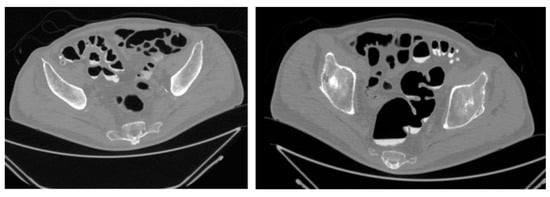

| Feature Evaluated | Virtual Colonoscopy Findings | 3D-Printed Model Findings |

|---|---|---|

| Extent of diverticulosis | Massive diverticulosis of sigmoid and descending colon | Same finding confirmed with clearer visualization of segmental involvement |

| Stenotic area | Suspected narrowing, poorly defined | Stenotic segment clearly delineated, with precise localization and extension |

| Anatomical relationships | Limited perception of spatial relations | Improved understanding of relationship between diseased colon and surrounding structures |

| Surgical planning implications | Suggestive of need for resection | Supported decision for left hemicolectomy |

| Tactile/spatial perception | 2D visualization only | Physical 3D model provided tactile and spatial feedback useful for team discussion and planning |